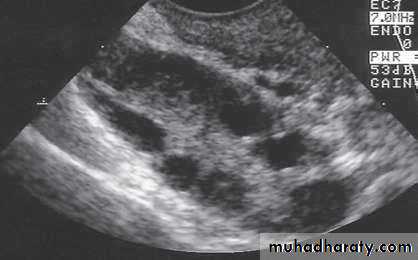

Ultrasound: increased stromal thickness and increased ovarian volume (>10 cm3)(specific for PCOS),and the presence of 12 or more follicles measured 2-9 mm in diameter.Serum endocrinology:

Ultrasound picture of polycystic ovary.